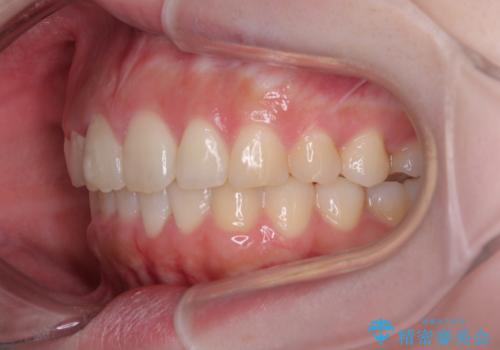

前歯のデコボコをインビザラインできれいに整える

前歯の捻れを改善するとともに、口元が少しでも引っ込むように治療計画を立て、仕上げることができました。

長時間の装着や、定期的な来院がままならず、想定よりも長期間の治療となってしまいました。